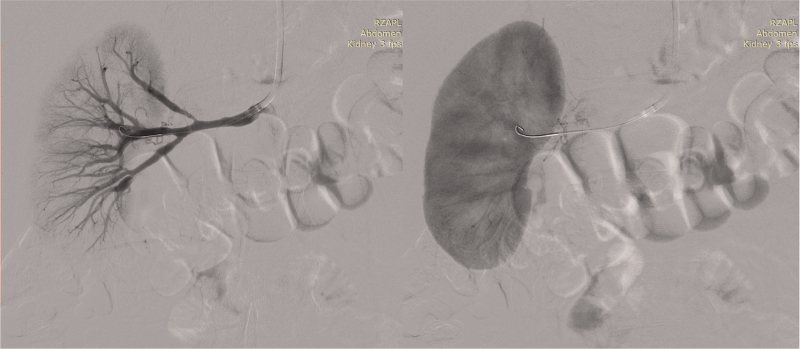

Abstract Image